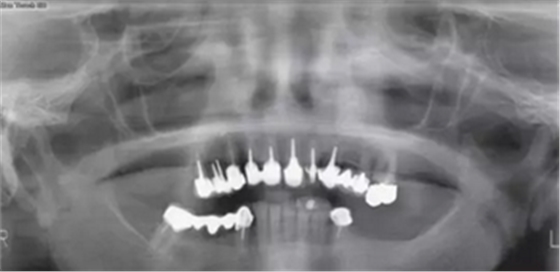

患者65歲,女性,非吸煙者,全身狀況欠佳,希望重獲咀嚼能力?;颊呶盖谐蟪霈F(xiàn)惡病質(zhì),消化功能受損,從而導(dǎo)致口腔狀況加重(圖1)。

圖1

患者3區(qū)磨牙缺失,#26冠修復(fù),頜曲線(xiàn)已改變。#13~15松動(dòng)3度(Lindhe和Muehlmanm分度)。牙根齲壞并根折,#14、15牙齦炎癥明顯但沒(méi)有膿腫和上頜竇炎。#47伸長(zhǎng),#47~43固定橋頜曲線(xiàn)異常。并沒(méi)有足夠的頜間距離能夠使#16作為拮抗。